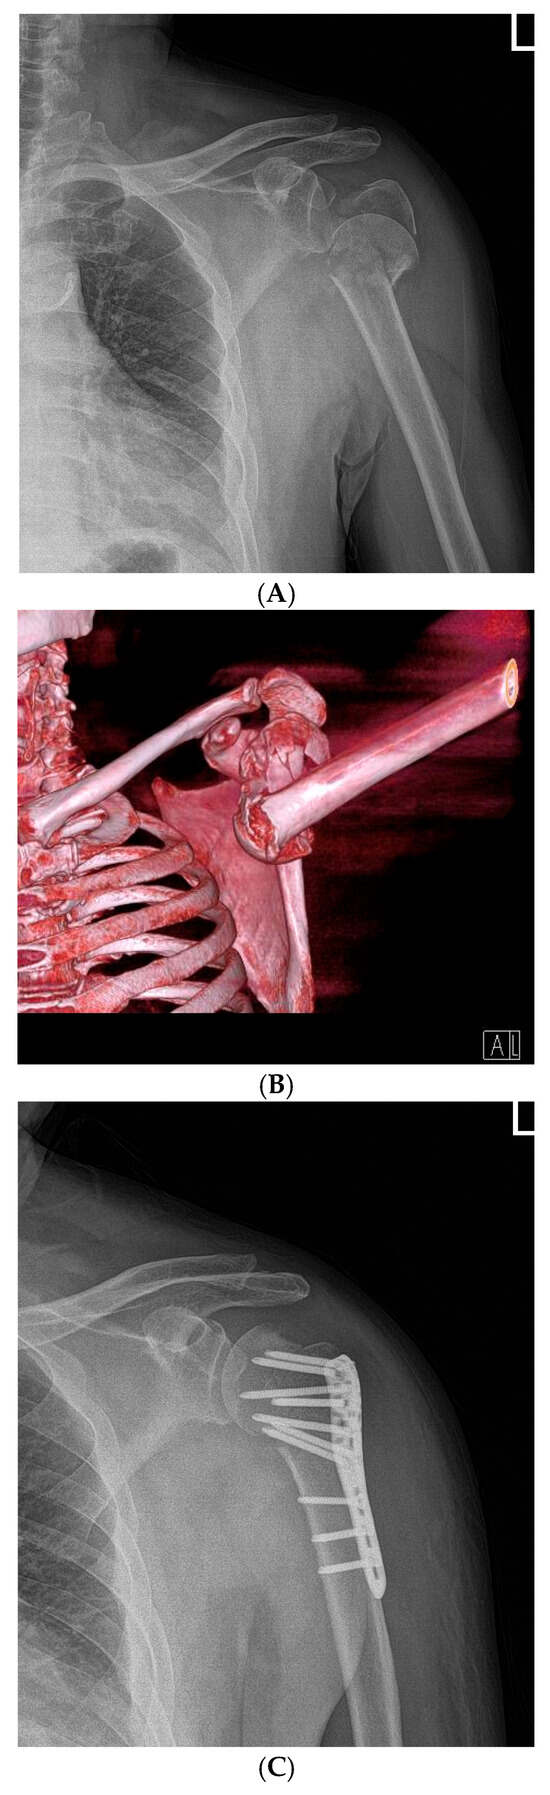

Figure 2.

Representative Case 1: 68-year-old female with Neer type-4 valgus impacted proximal humeral fracture treated with open reduction and internal fixation (ORIF) and early active rehabilitation. (A) Preoperative anteroposterior (AP) radiograph showing valgus impacted four-part fracture with medial hinge integrity preserved. (B) Preoperative 3D CT reconstruction confirming fracture pattern and displacement. (C) Immediate postoperative AP radiograph demonstrating anatomical reduction and stable fixation with proximal humeral locking plate (Double Medical, Xiamen, China). (D) 24-month follow-up AP radiograph showing complete fracture union with well-maintained reduction, no evidence of avascular necrosis or hardware complications.